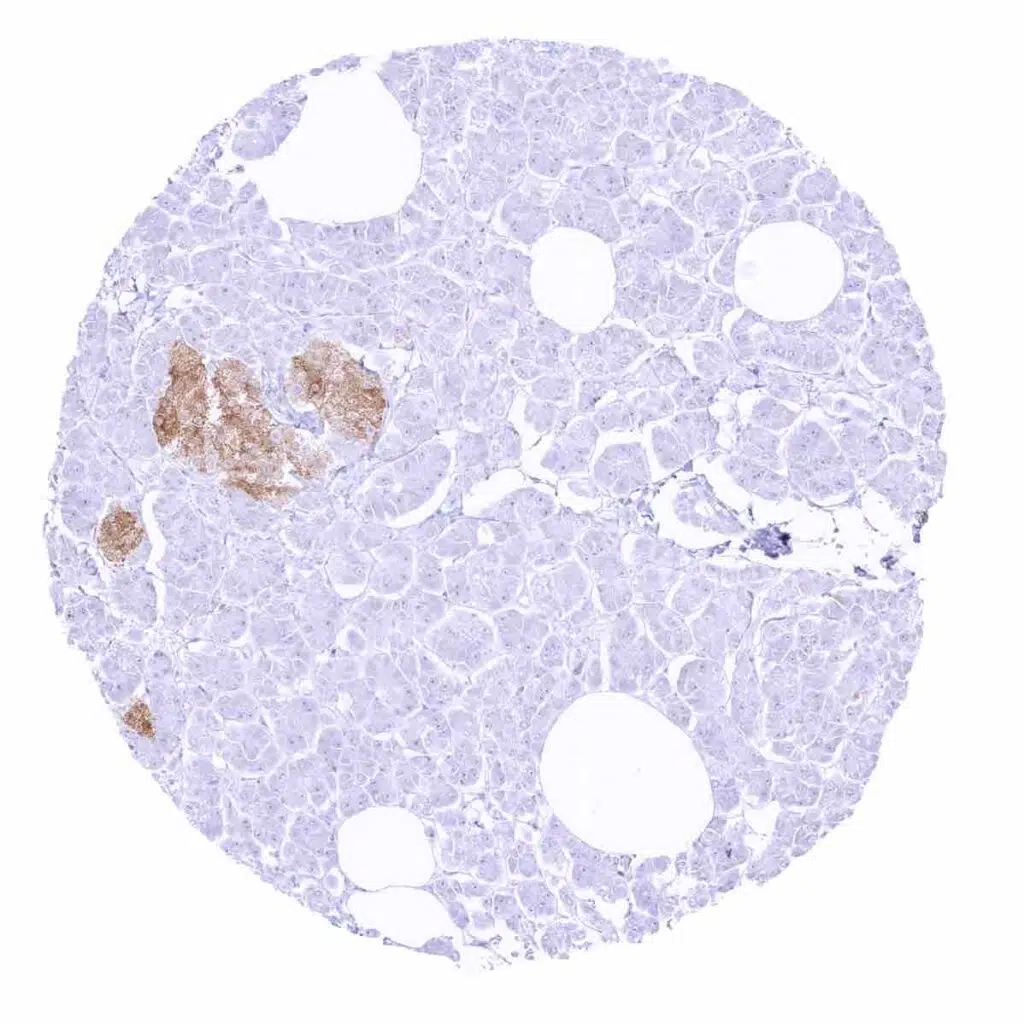

Pancreas – Strong cytoplasmic GAD65 staining of islet cells

Pancreas – Moderate intensity cytoplasmic GAD65 staining of islet cells